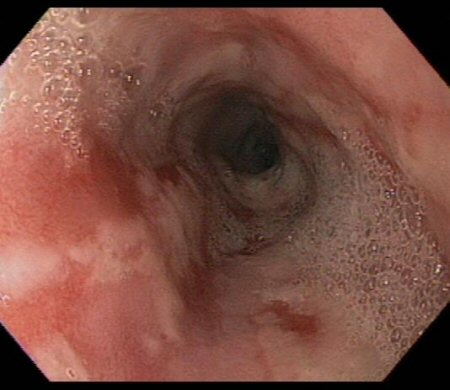

Moderate to severe oesophagitis with multiple linear, clean-based oesophageal ulcers

From the collection of Douglas G. Adler, MD